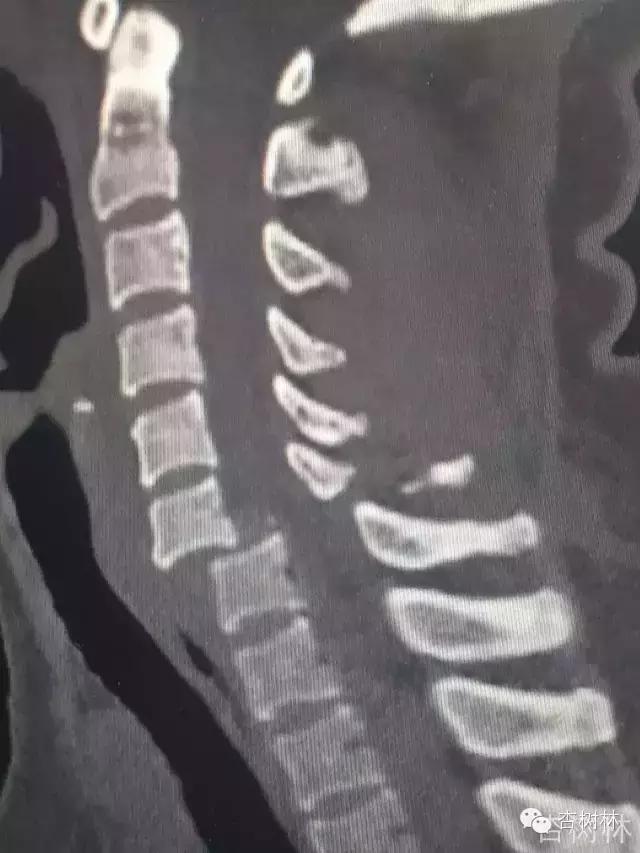

影像:急诊CT及MRI检查提示如下。

专家点评概述: 颈椎脱位 (C6-7 )伴不全瘫 ; 颈脊髓损伤 AISA B 级 ; C6-7 关节突关节绞锁(双侧)的关键点